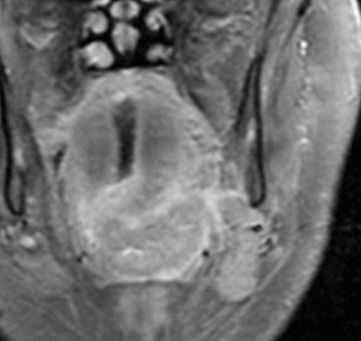

(Слева) МРТ Т1ВИ FS с КУ, аксиальная проекция. Лейомиосаркома жевательного пространства высокой степени злокачественности. Опухоль неоднородно накапливает контраст и прорастает в нижнюю челюсть. Только по данным лучевой диагностики дифференцировать различные типы сарком невозможно, за исключением случаев обнаружения матрикса остео- или хондросаркомы.

(Справа) МРТ Т1ВИ FS с КУ, коронарная проекция, тот же пациент. Новообразование, накапливающее контраст, распространяется в полость черепа через овальное отверстие. Отсюда опухоль может прорастать в пещеристый синус.в) Дифференциальная диагностика:

(Слева) МРТ Т1ВИ в аксиальной проекции. Саркома Юинга, локализующаяся в жевательном пространстве. Обратите внимание, что сигнал относительно здоровых мышц гиперинтенсивный. Нижняя челюсть разрушена, определяется лишь небольшой ее фрагмент. Жировая клетчатка окологлоточного пространства смещена в медиальную сторону.

(Справа) МРТ Т2ВИ FS, аксиальная проекция, тот же пациент. Неоднородный сигнал высокой интенсивности. Крупный лимфоузел в заглоточном пространстве слева представляет собой случайную находку.1. Общая характеристика: